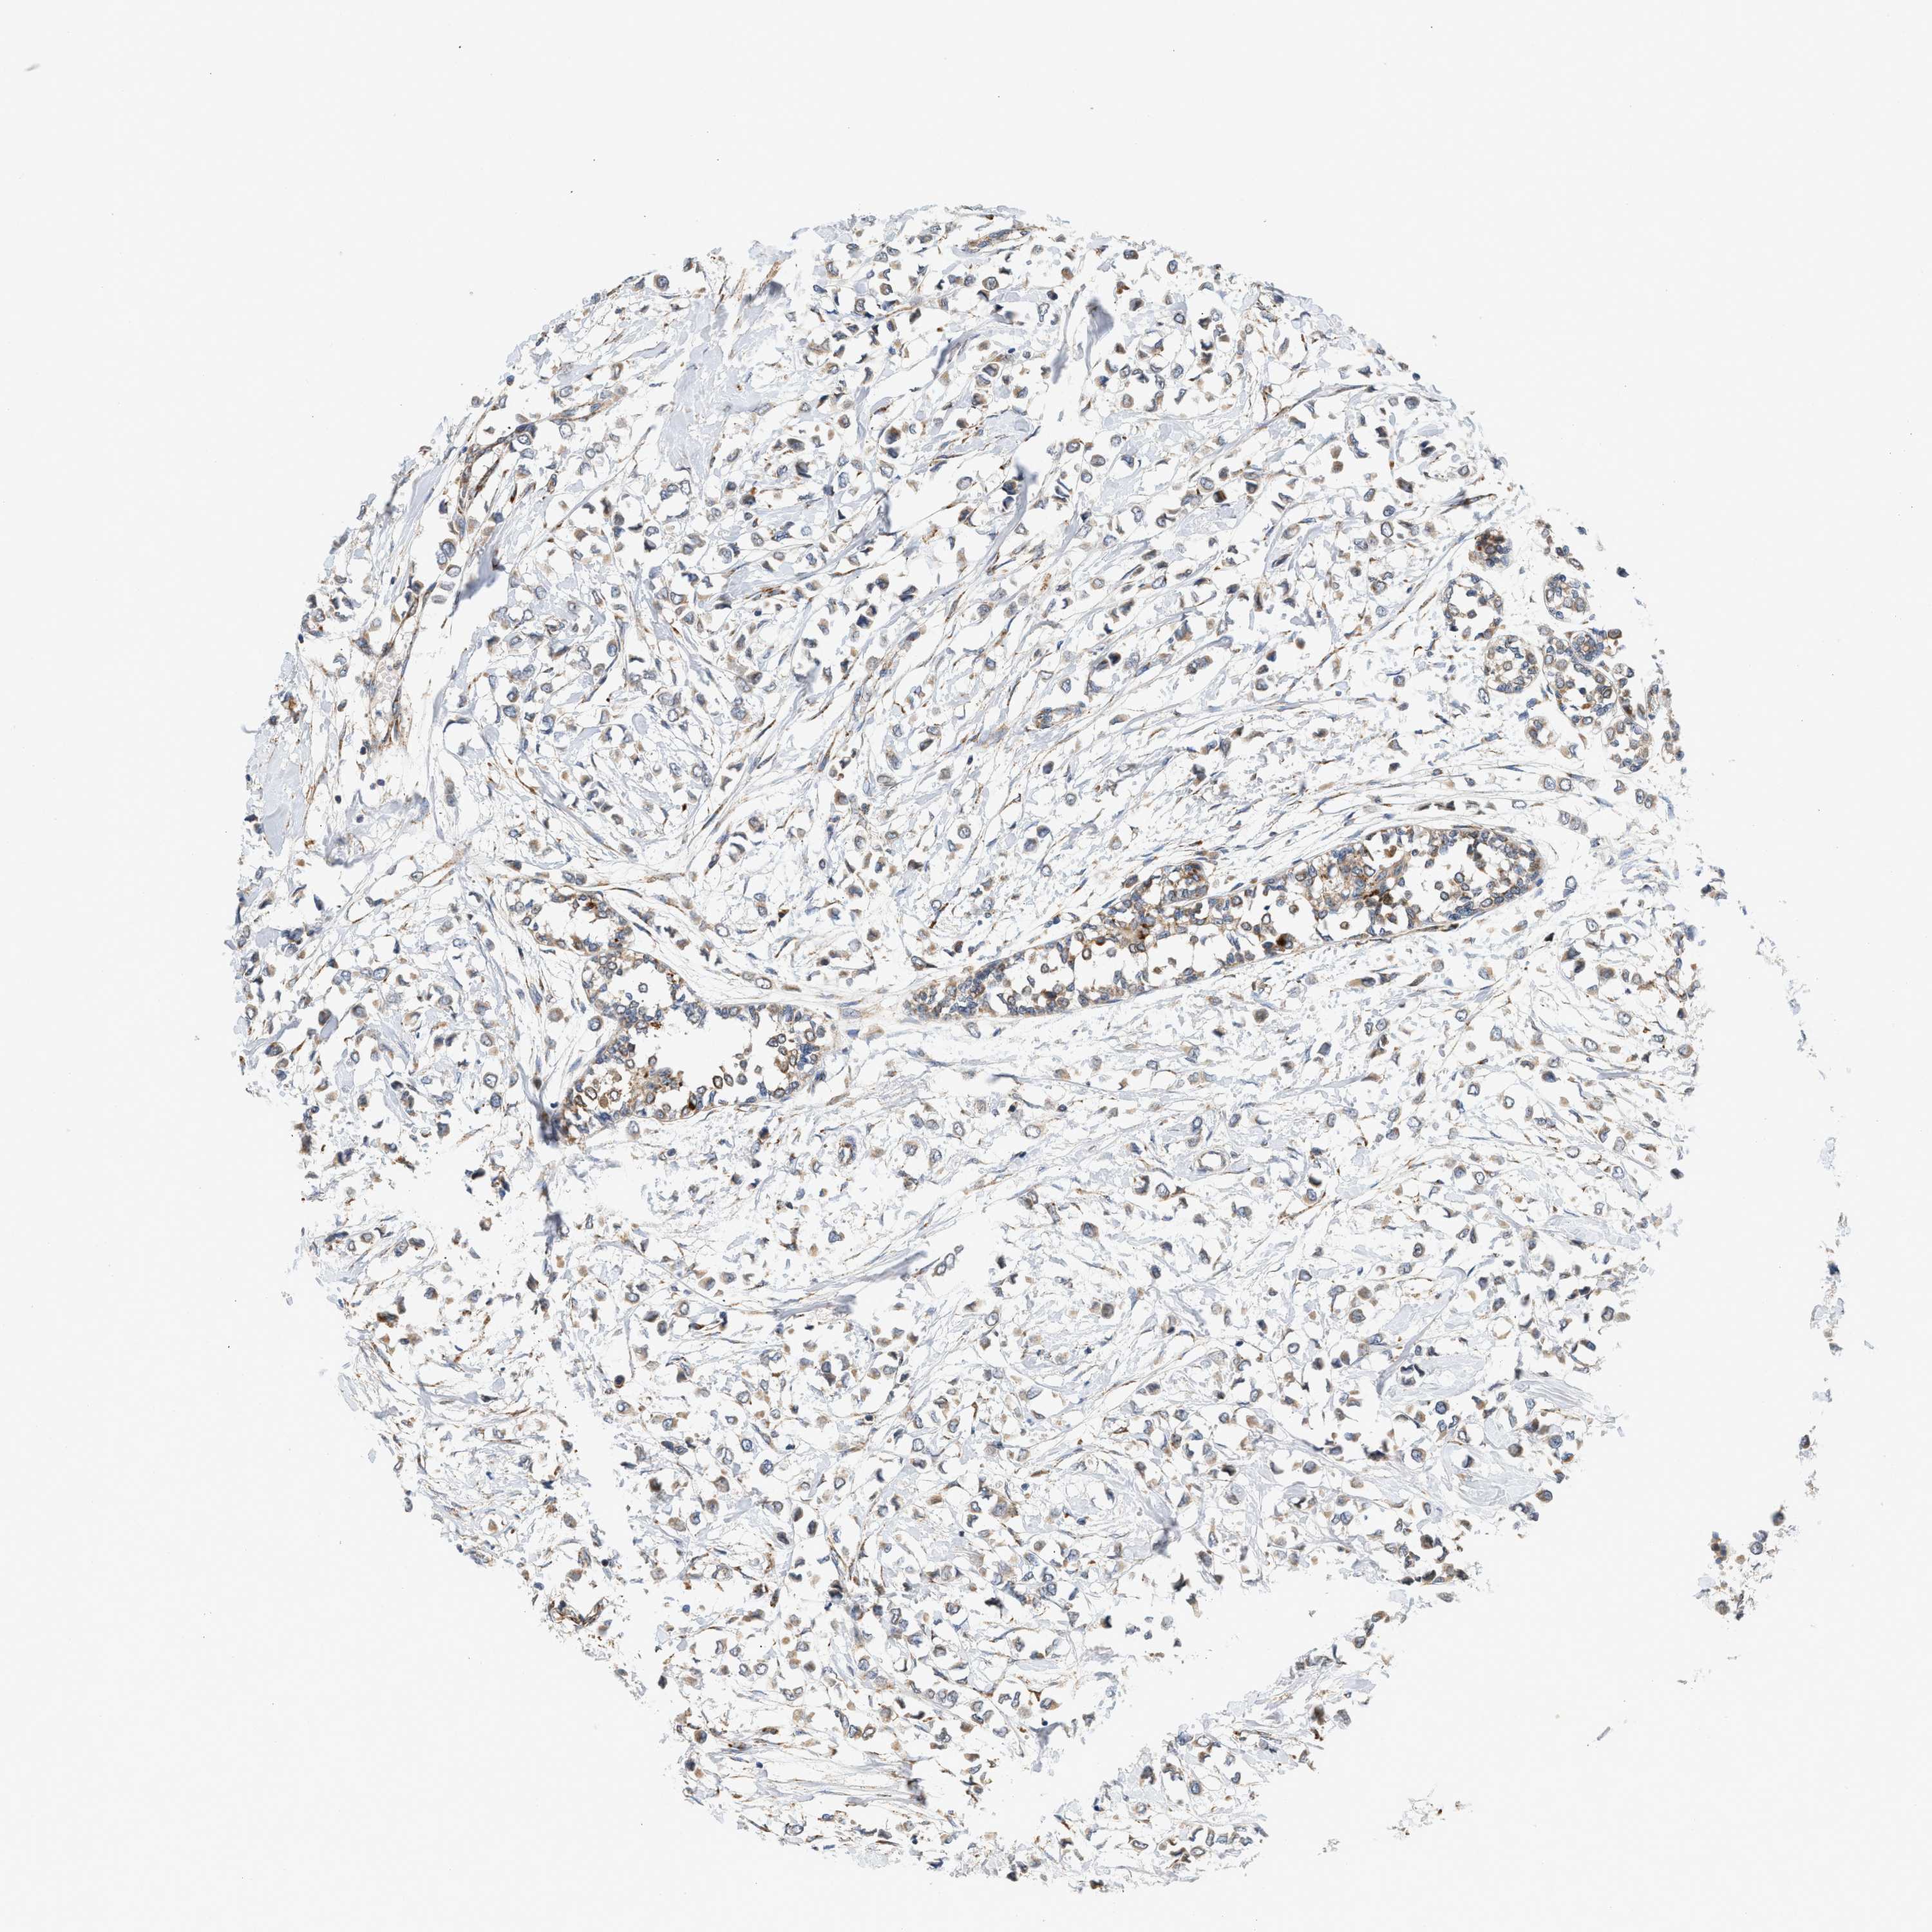

CANCER BREAST CANCER Show tissue menu

BRCA TCGA BRCA VALIDATION PROTEIN EXPRESSION